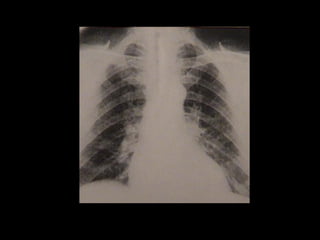

EXAMES

RADIOGRAFIA DE TÓRAX - aumento de VE

- ápice deslocado para baixo e à esquerda

EXAMES ECG- NORMAL HIPERTROFIA VENTRICULAR ESQUERDA RADIOGRAFIA DE TÓRAX - aumento de VE - ápice deslocado para baixo e à esquerda ECOCARDIOGRAMA - medida da área valvar - morfologia das câmaras direitas - Informações imprescindíveis ao diagnóstico, quantificação do volume regurgitante, anatomia das cúspides e da raiz aórtica, anatomia e função do VE. TE RNM VENTRICULOGRAFIA RADIOISOTÓPICA